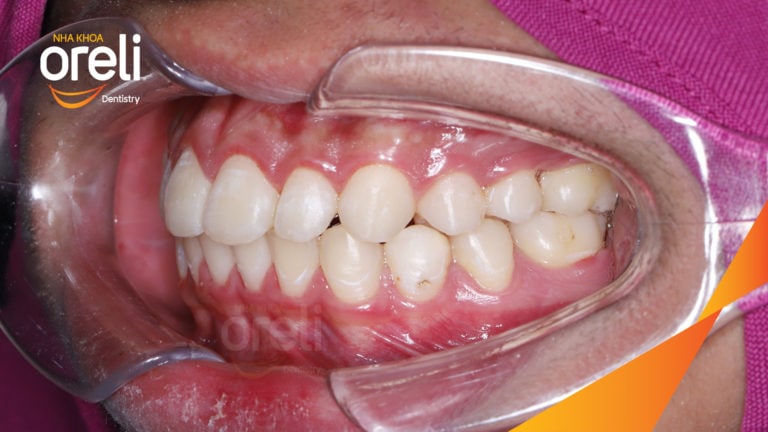

Ca niềng chỉnh cắn sâu nặng kèm cắn chéo vùng răng sau kết quả thực tế tại nha khoa Oreli Niềng răngCắn sâu Xem thêm